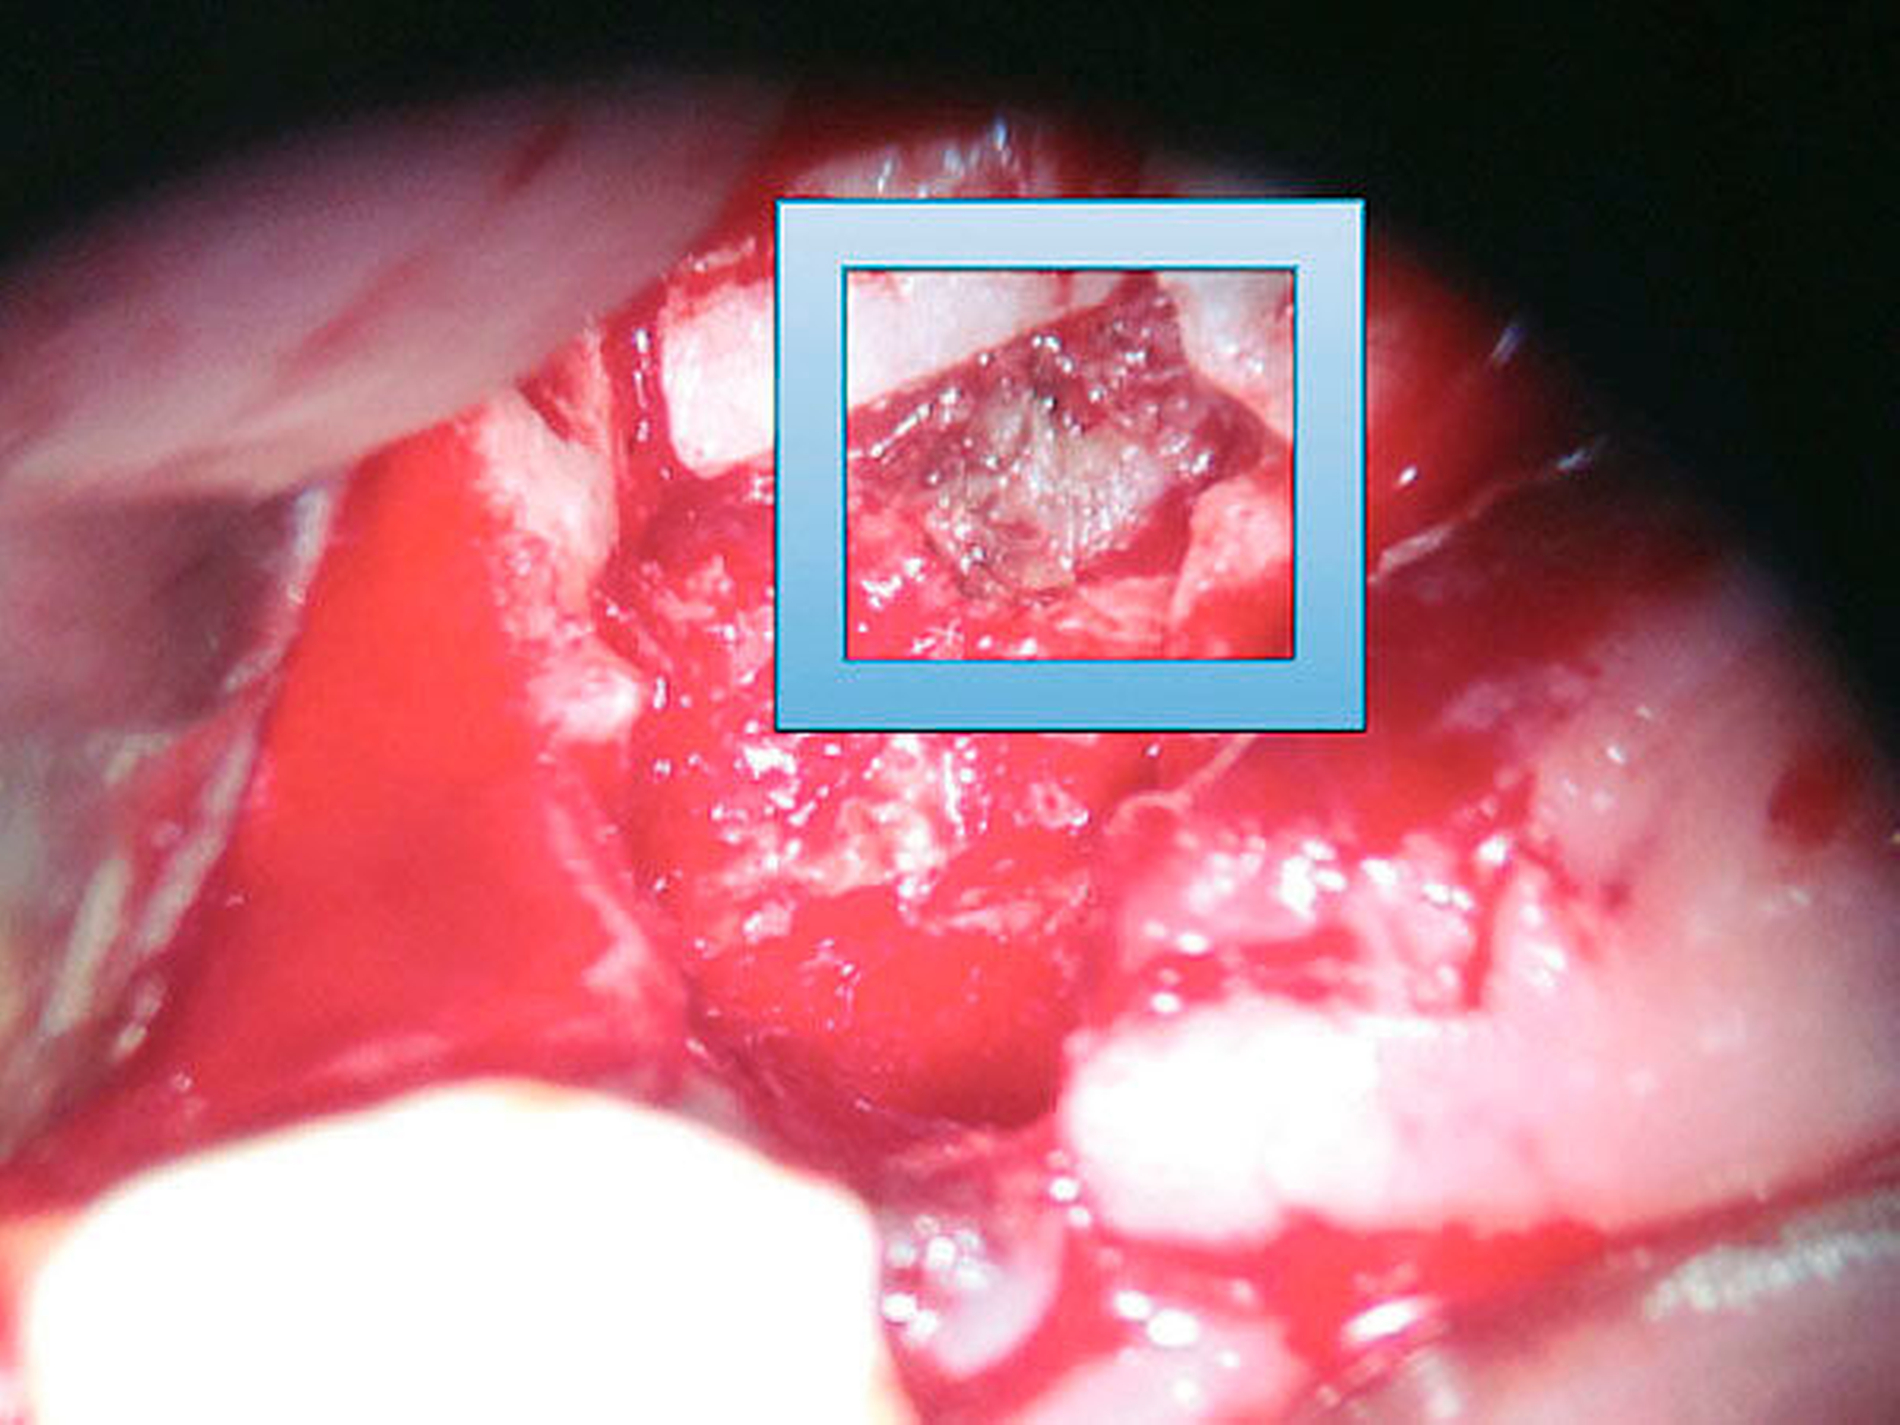

Leider gibt es keine Möglichkeit, Nerven nach außen wirksam darzustellen; daher ist eine explorative Operation erforderlich, und die Behandlungsentscheidung muss getroffen werden, während sich der Patient auf dem Operationstisch befindet [Kushnerev E, Yates JM, 2015]. Es gibt eine Reihe von Methoden, um Nervschäden zu reparieren. So kann je nach Bedarf gewählt werden zwischen externer Dekompression des N. alveolaris inferior (Abbildung 3) [Bagheri SC et al., 2012] , direkten Nervnähten [Cornelius CP et al., 1997] und der Rekonstruktion mit autologen Transplantaten (Nerven (N. suralis / N. aurikularis magnus) oder Venen) [Cornelius CP et al., 1997; Pogrel MA, Maghen A, 2001]. Weitere Möglichkeiten bestehen in der Anwendung von allogenen Manschetten um den beschädigten Nerv sowie in der großflächigen Freilegung, Mobilisation (Abbildung 4) und Readaptation der Nerven.